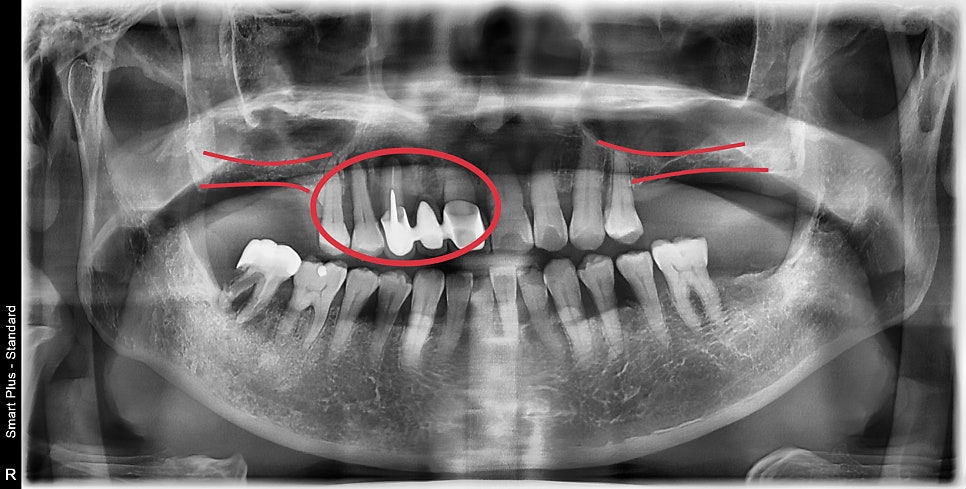

3D CT를 찍은 진단 결과입니다

어금니 쪽의 뼈의 두께가 너무 얇아 임플란트 수술을 위해서는

부비동이라고 알고 있는 상악동 공간에 임플란트 지지 공간을 만들어줘야 합니다.

이것이 상악동 거상술이라는 추가적인 술식이 필요한 이유입니다.

중간쪽 가장 심한 치주염이 진행된 치아 부분입니다.

빨갛게 표시된 부분이 뼈가 있어야 수술이 가능하지만

뼈이식을 동반하더라도 즉시 수술은 불가능한 상태였습니다.